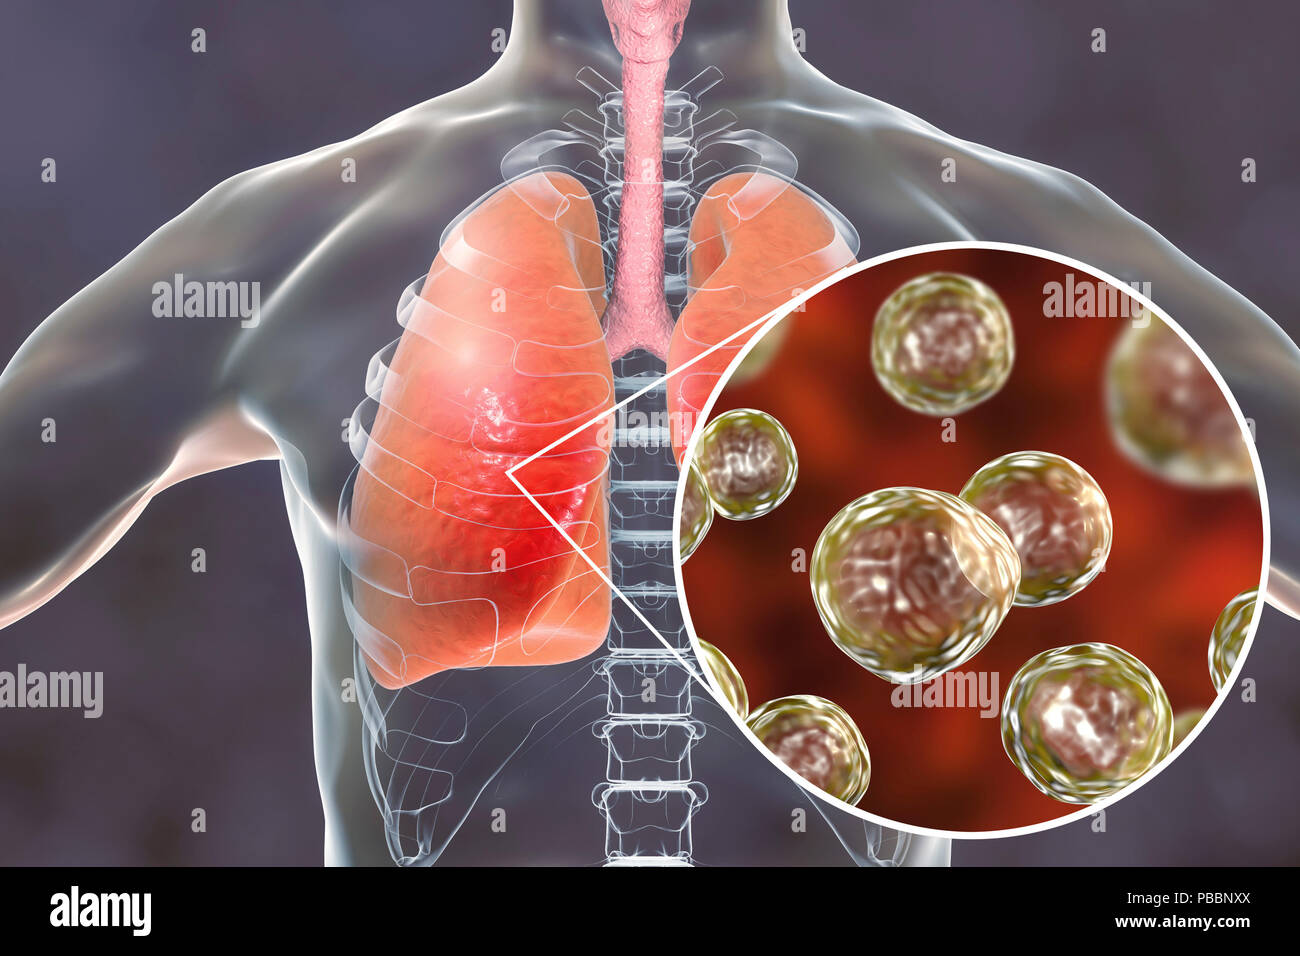

RFPBBNY0–La blastomycose pulmonaires, illustration conceptuelle. Blastomyces dermatitidis champignon est l'agent causal de la maladie de la blastomycose, qui dispose d'un éventail de présentations. Elle affecte principalement les poumons et peut causer une maladie semblable à la grippe, une maladie aiguë semblable à la pneumonie, une maladie chronique semblable à la tuberculose ou l'potentiellement fatals, le syndrome de détresse respiratoire aiguë. Dans certains cas, il peut s'étendre à la peau, des os ou des organes, causant des lésions. Le traitement est avec des médicaments antifongiques.

RFPBBNXX–La blastomycose pulmonaires, illustration conceptuelle. Blastomyces dermatitidis champignon est l'agent causal de la maladie de la blastomycose, qui dispose d'un éventail de présentations. Elle affecte principalement les poumons et peut causer une maladie semblable à la grippe, une maladie aiguë semblable à la pneumonie, une maladie chronique semblable à la tuberculose ou l'potentiellement fatals, le syndrome de détresse respiratoire aiguë. Dans certains cas, il peut s'étendre à la peau, des os ou des organes, causant des lésions. Le traitement est avec des médicaments antifongiques.

RFPBBNY3–La blastomycose pulmonaires, illustration conceptuelle. Blastomyces dermatitidis champignon est l'agent causal de la maladie de la blastomycose, qui dispose d'un éventail de présentations. Elle affecte principalement les poumons et peut causer une maladie semblable à la grippe, une maladie aiguë semblable à la pneumonie, une maladie chronique semblable à la tuberculose ou l'potentiellement fatals, le syndrome de détresse respiratoire aiguë. Dans certains cas, il peut s'étendre à la peau, des os ou des organes, causant des lésions. Le traitement est avec des médicaments antifongiques.